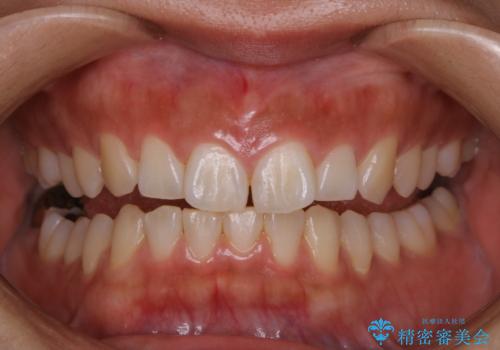

矯正治療前にホワイトニング

- 矯正治療前にホワイトニングがしたいとのことで来院されました。

処置前クリーニングとオフィスホワイトニングのエクセレントコースを行いました。

処置前クリーニングとオフィスホワイトニングのエクセレントコースを1回行いました。

この患者様は、歯科矯正に1、2年かかり矯正中はホワイトニングをすることが出来ないため、歯を白くしてから矯正治療にすすみたいとのことでオフィスホワイトニングを行いました。1回の施術で2.3トーン白くなり、とても白くなりました。ホワイトニングは何度も重ねて白くしていくのですが、1度で満足のいく色見になったため一旦様子を見ることにしました。